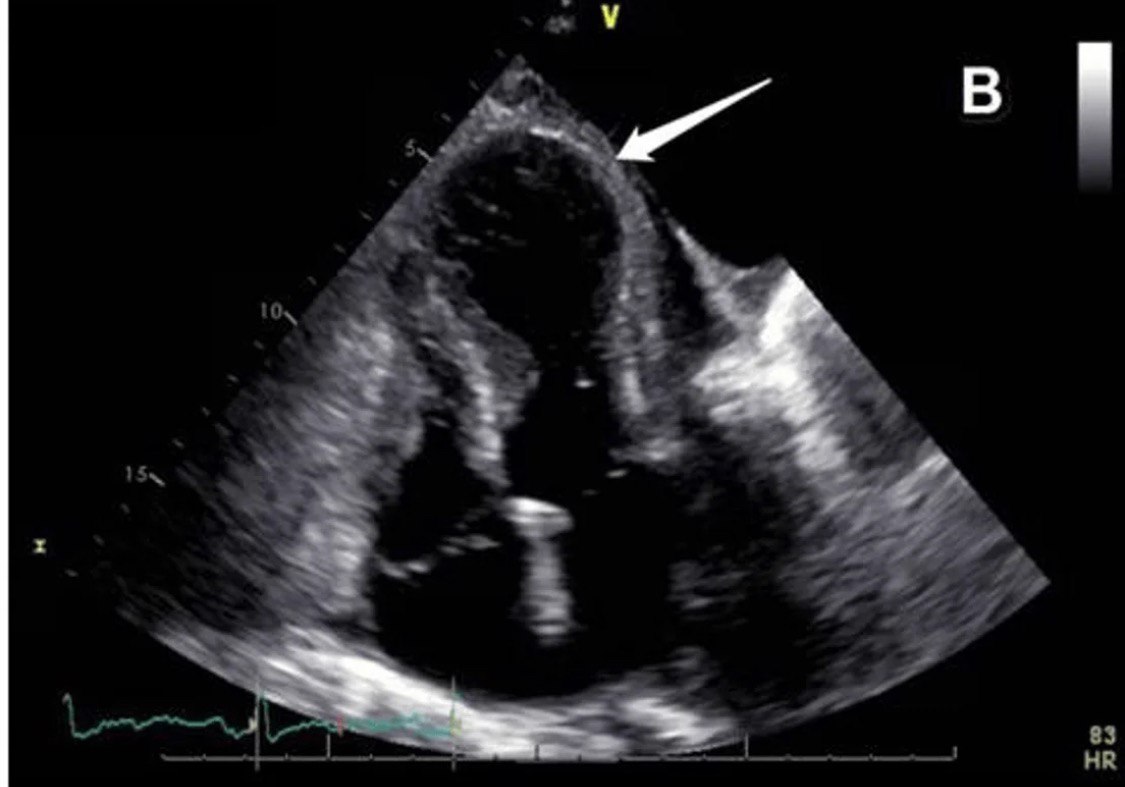

Знаете ли вы, какая патология на эхограмме и почему ее еще называют ловушкой для осьминогов?